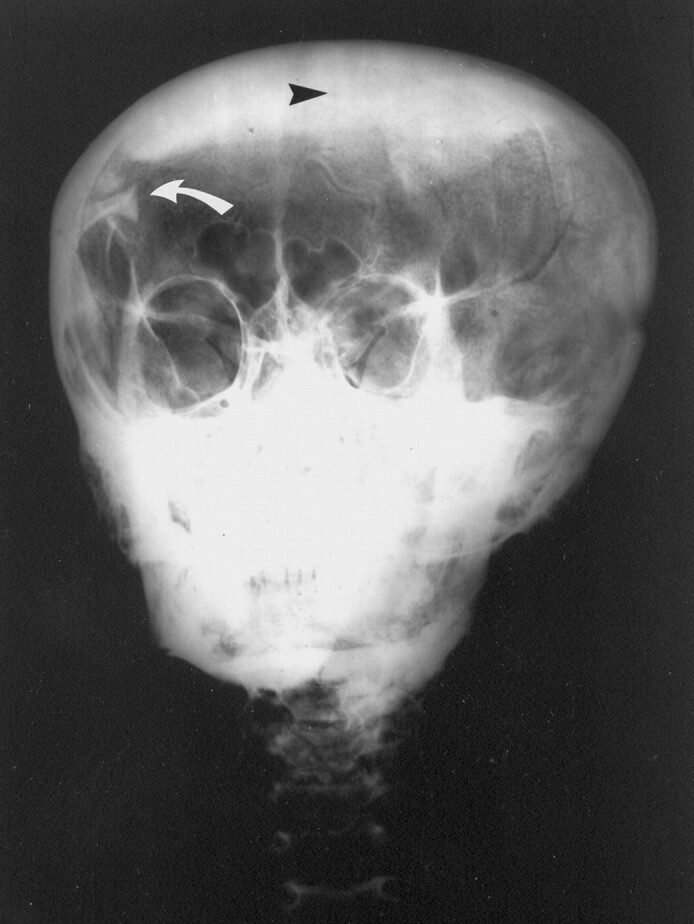

Fig 2.

Frontal radiograph of Tutankhamen’s skull and cervical spine shows the opaque layer of resin in the vertex region (arrowhead) and the bone fragment (curved arrow). Note that the second fragment is not apparent in this image. (Reprinted courtesy of the University of Liverpool.)

The cranial-facial proportion appeared appropriate for a young adult male. The calvaria appeared to be intact. No skull fracture was identified. However, as discussed by Harrison (2, 4), two fluid levels were present, which resulted from the resin introduced at the time of embalming. The resin deposits in the vertex and occipital regions of the cranial vault were well seen on the lateral view radiograph (Fig 1). The resin in the vertex was seen on the frontal view radiograph (Fig 2). The sub-mental vertex view showed the resin in the occipital region (Fig 3). The presence of this hardened, opaque resin was actually helpful in understanding and refuting the commonly held theories of skull fracture and subdural hematoma.

Careful inspection of the radiographs showed that there are, in fact, two intracranial bone fragments, which are in the right parietal/occipital area, not on the left, as suggested by Harrison. These fragments are separate from the attenuated shadows of the intracranial resin. No other bone fragments or abnormal intracranial contents were detected. The nasal-ethmoid-cribriform plate region appeared to be intact. No fracture or missing parts were noted, in distinction from Harrison’s observations. Radio-attenuated material was also seen in both nasal passages. These plugs were placed in the nasal passages to seal the intracranial vault after the embalmers had removed the brain and cauterized the inside of the skull with hot resin, presumably to prevent leakage of resin or liquefied brain. Careful inspection of the bone fragments shown on all three images indicated that the larger of the bone fragments appeared to be a portion of the posterior arch of the first cervical vertebra.

Reeves (8) and Brier (1) previously published in the lay literature a photograph of the lateral view radiograph of Tutankhamen showing the bone fragment(s). However, the complete set of three radiographs of Tutankhamen’s skull and cervical spine has not been previously published or made available to the scientific community for review. Two bone fragments were noted within the calvaria, a finding not mentioned by other observers. It is not clear why Harrison reported that the fragments were on the left side, when they were clearly on the right. Connolly, a member of the Harrison expedition, confirmed that the markings on the radiographs were correct and that the fragments were thus on the right. If these had been dislodged from the calvaria by a blow causing a skull fracture before death, the fragments would have been imbedded in the resin, which was instilled after death, and hence the fragments would not be visible on the radiographs. Alternatively, it has been suggested that the fragments may have been dislodged in the embalming process, but similar logic applies. Had the embalmers dislodged the fragments, they would have been buried in the resin, which was poured in after the intracranial contents were evacuated. Furthermore, there is no visible donor site in the cribriform plate region, as suggested by Harrison, to suggest a fracture in this region. The nasal plugs placed after instilling the resin were observed to be intact. It is most likely that the fragments were dislodged, not at the time of embalming but at the time of the autopsy performed by Derry and his associates in 1925. This assumption is supported by a set of radiographs obtained in 1978 by J.E. Harris of the University of Michigan (personal communication). These images showed that the bone fragments were no longer in the superior parietal region but near the base of the skull. The mobility of the fragments within the cranial vault indicated that they were not fixed to the skull or resin but were freely moveable, consistent with postmummification trauma.